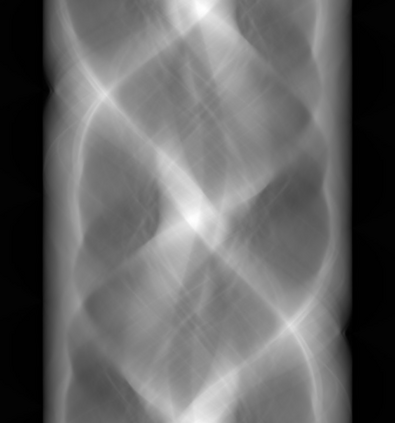

Sparse-view computed tomography (CT) -- using a small number of projections for tomographic reconstruction -- enables much lower radiation dose to patients and accelerated data acquisition. The reconstructed images, however, suffer from strong artifacts, greatly limiting their diagnostic value. Current trends for sparse-view CT turn to the raw data for better information recovery. The resultant dual-domain methods, nonetheless, suffer from secondary artifacts, especially in ultra-sparse view scenarios, and their generalization to other scanners/protocols is greatly limited. A crucial question arises: have the image post-processing methods reached the limit? Our answer is not yet. In this paper, we stick to image post-processing methods due to great flexibility and propose global representation (GloRe) distillation framework for sparse-view CT, termed GloReDi. First, we propose to learn GloRe with Fourier convolution, so each element in GloRe has an image-wide receptive field. Second, unlike methods that only use the full-view images for supervision, we propose to distill GloRe from intermediate-view reconstructed images that are readily available but not explored in previous literature. The success of GloRe distillation is attributed to two key components: representation directional distillation to align the GloRe directions, and band-pass-specific contrastive distillation to gain clinically important details. Extensive experiments demonstrate the superiority of the proposed GloReDi over the state-of-the-art methods, including dual-domain ones. The source code is available at https://github.com/longzilicart/GloReDi.